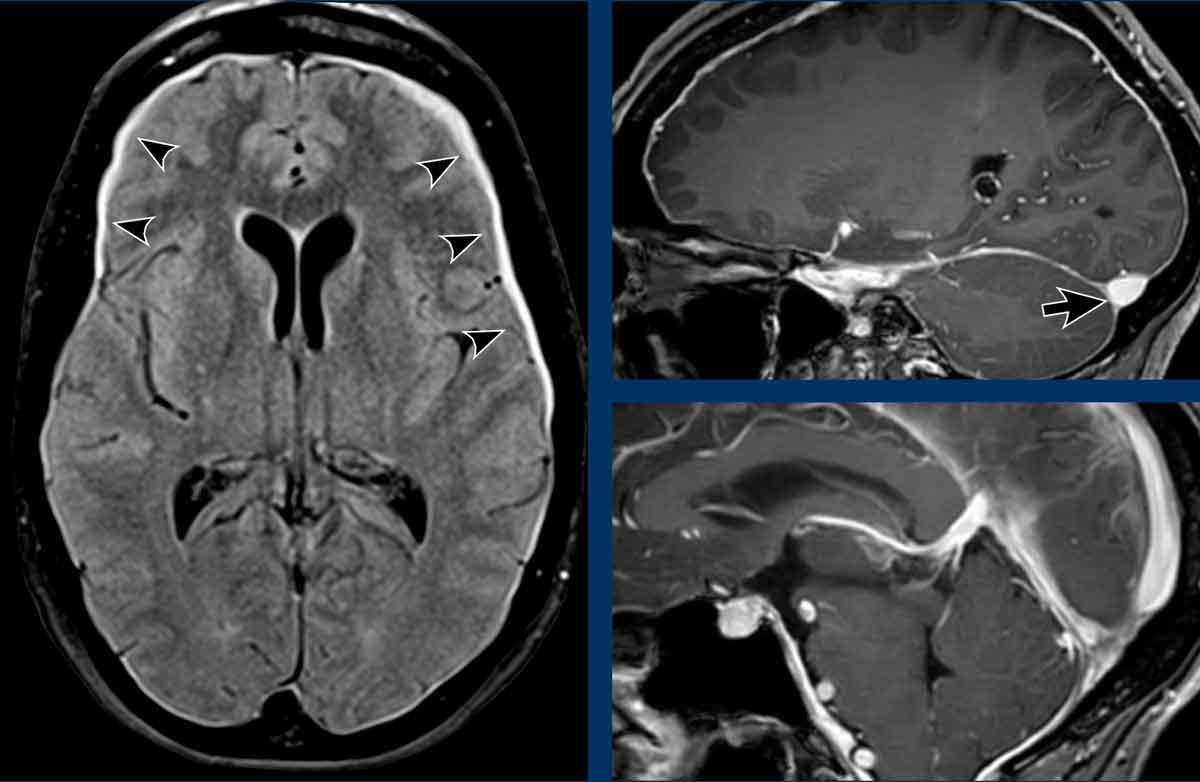

Ở bệnh nhân SIH này, tất cả các tĩnh mạch đều giãn và bờ của xoang tĩnh mạch ngang có dạng lồi.

Lưu ý thêm hình ảnh màng cứng dày và ngấm thuốc.

Chuỗi xung FLAIR cho thấy các đặc điểm điển hình của hạ áp nội sọ tự phát:

- Giãn tĩnh mạch và xoang tĩnh mạch màng cứng

- Trung não bị võng xuống mức độ nhẹ

- Giảm khoảng cách thể vú – cầu não

- Tràn dịch dưới màng cứng hai bên trên chuỗi xung FLAIR axial (đầu mũi tên).

- Giãn tĩnh mạch và xoang tĩnh mạch màng cứng với bờ dưới lồi của xoang ngang (mũi tên đen).

- Trung não bị võng xuống và khoảng cách thể vú – cầu não giảm.